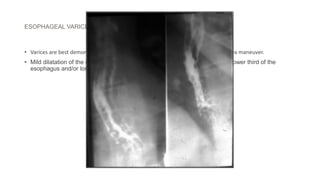

ESOPHAGEAL VARICES

• Varices are best demonstrated in mucosal relief study after using Buscopan/ valsalva maneuver.

• Mild dilatation of the esophagus with multiple persistent filling defects in the lower third of the

esophagus and/or longitudinal furrows.